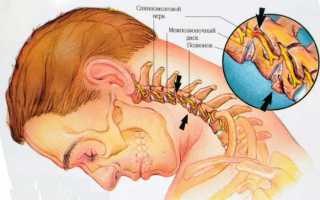

Вот они:

- подвывихи шейных позвонков и спондилолистез (вызывают деформацию позвоночного канала);

- остеохондроз (костные разрастания начинают сжимать артерию);

- окостенение, затрагивающее мембрану между позвоночником и затылком;

- образование тромбов в аномальной артерии;

- атеросклероз сосудов.

Хирургическое вмешательство

Применяется исключительно в экстренных ситуациях, когда становится ясно, что восстановить нормальный кровоток в мозге невозможно. Современные нейрососудистые хирурги предпочитают использовать эндоваскулярные вмешательства. Суть этого подхода заключается во введении стента (специального устройства для расширения) в просвет суженной позвоночной артерии.

Стент увеличивает диаметр пораженного участка, который претерпел патологические изменения, что способствует восстановлению нормального кровоснабжения. Процедура во многом схожа с ангиографией, поэтому часто выполняется одновременно с этим диагностическим методом.